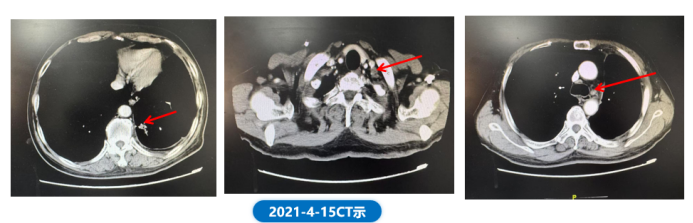

• 2021.04.15 胸腹CT示,与前比较,左下肺病灶较前变化不大,左侧锁骨上(1.33cm*1.54cm缩小至1.05cm*1.30cm)及纵膈、左肺门多发饱满及稍肿大淋巴结,部分较前稍缩小。余胸、腹部情况较前变化不大。

肺“长”实“例” :从真实世界病例看EGFR ex20ins NSCLC患者综合治疗模式下的长生存漫漫路2078.png